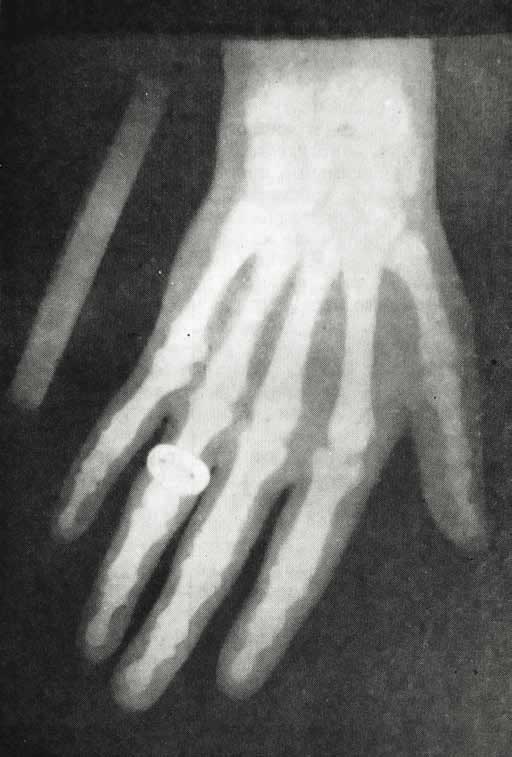

Рентгеновский снимок руки А. С. Попова. 1896 г. (Центральный музей связи имени А. С. Попова.)

Раиса Алексеевна была врачом-новатором, смело внедряла новые методы лечения и диагностики. А. С. Попов первым на военно-морском флоте сконструировал рентгеновскую установку, собственноручно сделал трубку Крукса – выдул трубку из стекла, впаял в нее контакты и выкачал воздух. К началу 1896 г. относятся работы Попова в области только что открытых рентгеновских лучей. Уже в феврале им был изготовлен один из первых в России рентгеновских аппаратов, получены снимки различных предметов, в том числе снимок руки человека. При его поддержке в Кронштадтском военно-морском госпитале в 1897 г. был оборудован рентгеновский кабинет, и Раиса Алексеевна помогала в эксплуатации этой установки. Впоследствии некоторые боевые корабли были оснащены рентгеновскими аппаратами. Известно, что после сражения в Цусимском проливе на крейсере «Аврора», имевшем такую установку, была оказана помощь 40 раненым морякам.